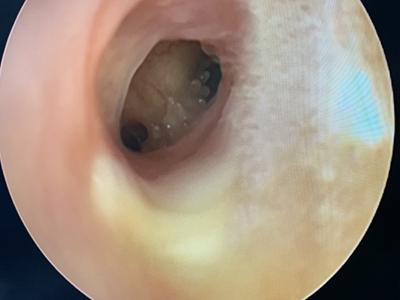

霉菌性外耳道炎耳朵里发红肿胀图

霉菌性外耳道炎患者的一侧外耳道黏膜充血、肿胀,可见细密的白色、灰色丝状物,覆盖在靠近鼓膜处,并伴有耳内发痒症状,夜间为甚。